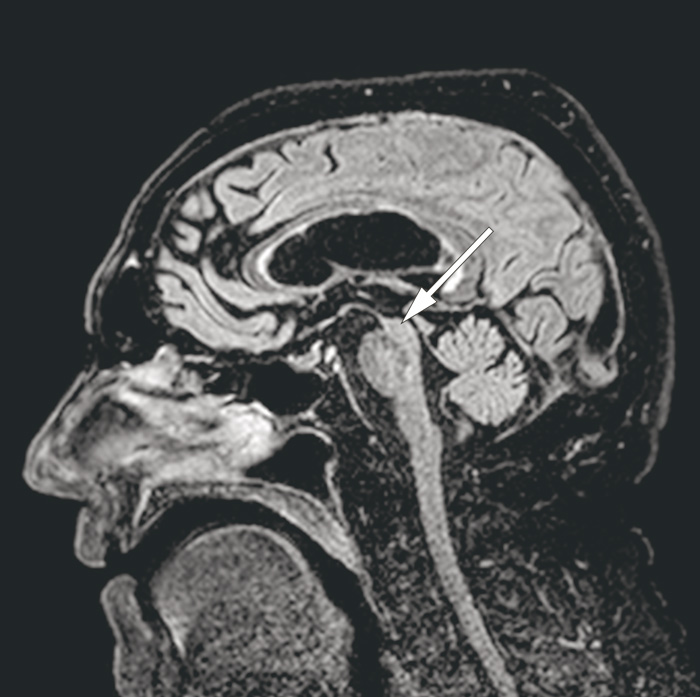

MR-undersøkelse av hjernen viste en uttalt atrofi av mesencephalon som i sagittalsnitt får hjernestammen til å ligne en fugl i profil, gjerne omtalt som kolibritegn eller pingvintegn (pil). Dette er et typisk bildefunn ved den sjeldne nevrodegenerative tilstanden progredierende supranukleær parese (1).

Tilstanden inngår i fellesbetegnelsen atypisk parkinsonisme, en gruppe sjeldne nevrodegenerative tilstander som bør vurderes dersom parkinsonisme opptrer med uvanlige trekk og/eller tilleggssymptomer. Flere av sykdommene har karakteristiske MR-funn som ofte er nøkkelen til at diagnosen stilles (2).